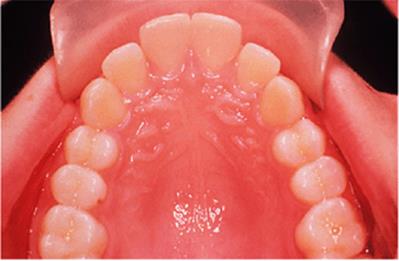

Before discussing functional appliances in detail, Fig. 18.1 gives an overview of this type of functional appliance in clinical use. This patient has a Class II division 1 malocclusion of the type for which functional appliances are very suitable, and for which they have been used for many years.

There are a number of important features to note which will be discussed further later in the chapter. First, the patient is still growing and the signs are that her pattern of facial growth is likely to be favourable. Although the skeletal pattern is Class II, the vertical relationships are close to average and the direction of mandibular growth is likely to be a mild forward rotation (see Chapter 4) which is favourable to the correction of a Class II malocclusion. Second, the soft tissue morphology is favourable despite the lips being incompetent, with the lower lip resting behind the upper incisors. The lower lip line is above the level of the upper incisal edges, and after the overjet has been reduced the lower lip will rest labially to the upper incisors, so helping to resist any tendency for relapse of the overjet. Third, the arches are well aligned — functional appliances have no mechanism for treating irregularities of alignment of the teeth.

Fig. 18.1. (a) This 12-year-old girl had a skeletal II facial pattern and average facial proportions. The lips were incompetent with the lower lip lying below the upper incisors at rest. (b), (c) She had a Class II division 1 malocclusion with an overjet of 10 mm, the overbite was increased and complete, and the molar relationship was Class II on both sides. (d), (e) The upper and lower arches were well aligned. (f) A functional appliance (an activator) was fitted. (g) The corrected occlusion with Class I incisor and molar relationships. (h) The patient's facial profile at the end of treatment.